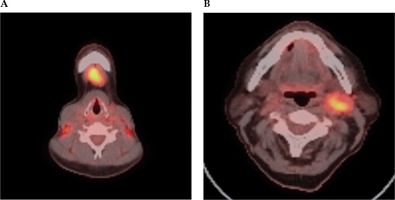

Fig. 3

FDG PET-CT scan selected axial slices, which demonstrate high grade FDG activity within a submental IA lymph node (A) and left level 2 lymph node (B) in a case of unknown primary cancer. A) Axial PET-CT imaging demonstrates high grade FDG activity within a submental 1A lymph node. B) Axial PET-CT imaging demonstrates high grade FDG activity within a left level 2 lymph node